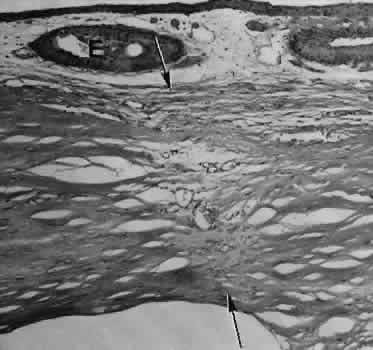

Epithelial downgrowth (ingrowth) (Fig. 44) is one of the most serious causes of pseudophakic glaucoma, in which surface epithelium (probably from the conjunctiva) grows into the anterior chamber. This condition is more likely to occur with fornix-based conjunctival flaps than with limbus-based flaps and in eyes with problems in wound closure, such as vitreous loss, wound incarceration of tissue, delayed reformation of the anterior chamber, or frank rupture of the limbal incision, and when instruments such as iridectomy forceps are contaminated with surface epithelium before they are introduced into the eye. Epithelial downgrowth causes an anterior chamber angle closure by means of peripheral anterior synechiae or lines an open anterior chamber angle and obstructs aqueous outflow mechanically. Histologically, the epithelium is seen to grow most luxuriously and in multiple layers on the iris where there is a good blood supply, but it tends to grow sparsely and in a single layer on the posterior surface of the avascular cornea. The epithelium may extend behind the iris, over the ciliary body, and even far into the interior of the eye.

Fig. 44. A case of epithelial downgrowth. A. The clinical findings are subtle and consist of a translucentmembrane on the posterior corneal surface, often contiguous with an ocular wound, characterized by a well-defined, linear leading edge. In this case, the leading edge is just above the corneal light reflex. B. In contrast, in this case, the leading edge is just below the corneal light reflex. The surgical procedure in both cases appears to have been complicated because of the presence of sector iridectomies. C. In this case, surface stratified squamous epithelium lines the posterior cornea (including the posterior aspect of the clear corneal wound) and extends over delicate trabecular tissue onto the anterior surface of the iris. The epithelium will adapt the tissue over which it grows to produce an adhesive surface appropriate to its attachment requirements. This adaptive process that is an advantage for the epithelium will permanently destroy the function of the trabecular meshwork over which the surface epithelium extends. D. The actual site of the fistula allowing the epithelium to gain access to the internal surfaces of the eye is rarely found on histologic sections. Higher magnification of the area of the wound, however, does show the presence of foreign material in the incision. Polarized material (inset) consistent with degenerating silk suture is present. Invasion of the epithelium along a suture tract is one possible route of entrance. (Hematoxylin-eosin stain with and without polarization; A, × 21; B, × 101)